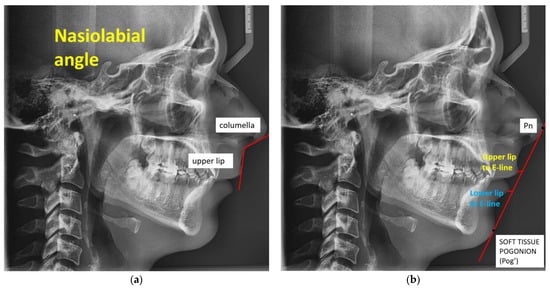

| Nasolabial angle (degrees) | 101 (97, 110) |